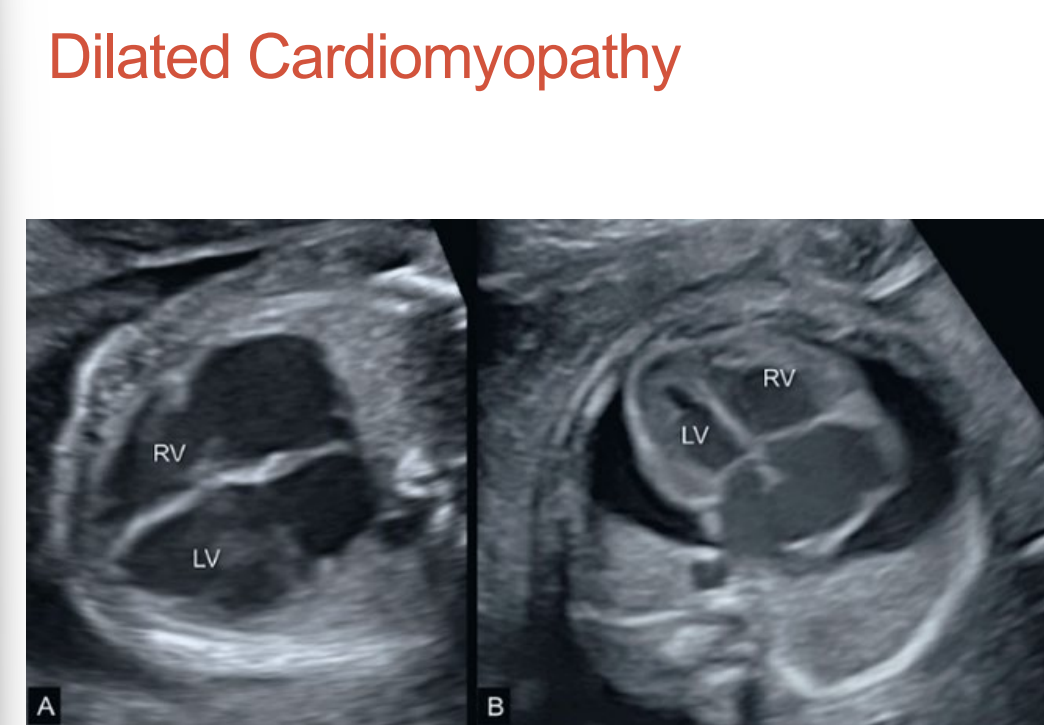

Dilated Cardiomyopathy

All four chambers dilate •

Usually has inflow regurgitation •

Decreased wall contraction •

Pericardial effusion is a common finding • May lead to hydrops •

Associated with maternal infections, autoantibodies, parvovirus, and complete heart block